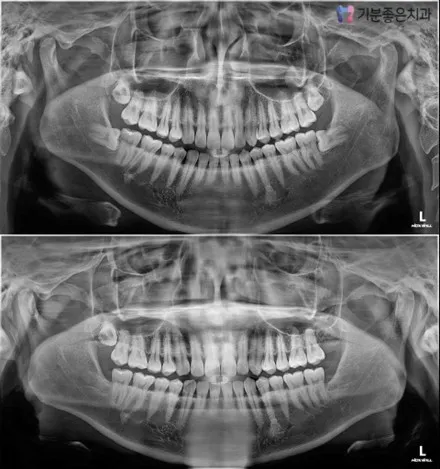

Types of Wisdom Teeth and Treatment Decisions

Treatment methods and difficulty vary significantly depending on the direction and position of wisdom tooth growth.

Normally Erupted Wisdom Teeth

These are wisdom teeth that erupt properly through the gum line, with relatively normal alignment relative to surrounding teeth. Whether to retain or extract them depends on their maintenance status.